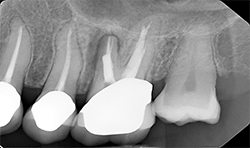

Periapical radiographs (Figs. 8A, 8B) show that radiolucent area around the mesial root of #14 and missing lamina dura. The apical lesion is close to the floor of the left maxillary sinus.

Fig. 8A

Fig. 8B